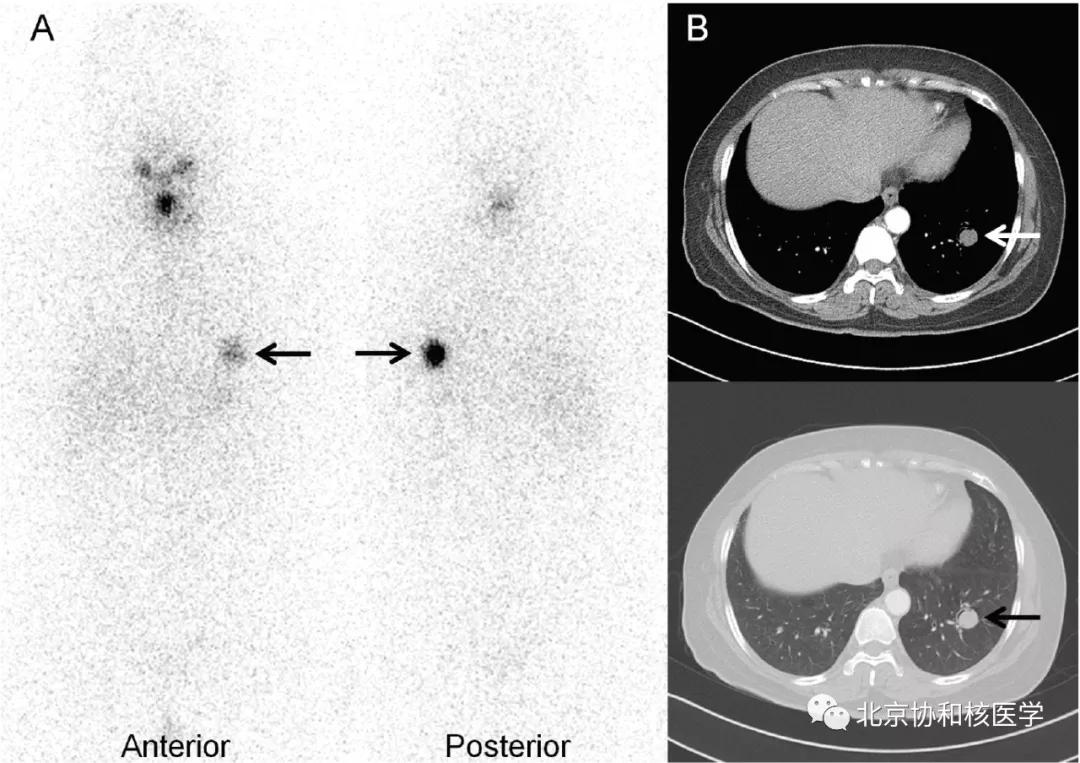

脑膜瘤所致碘摄取:

鼻骨骨样骨瘤所致碘摄取,腹部另可见由于巨大肾囊肿所致碘异常摄取: